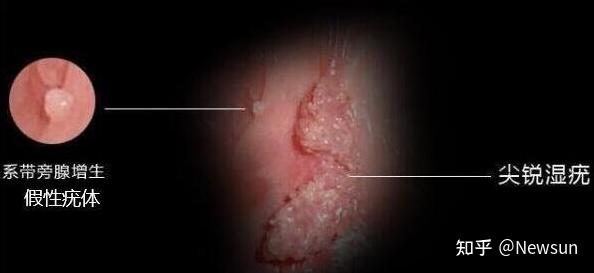

(内附图片) newsun 女阴假性湿疣是一种正常的生理变异,并非病态,也有

图片尺寸594x273